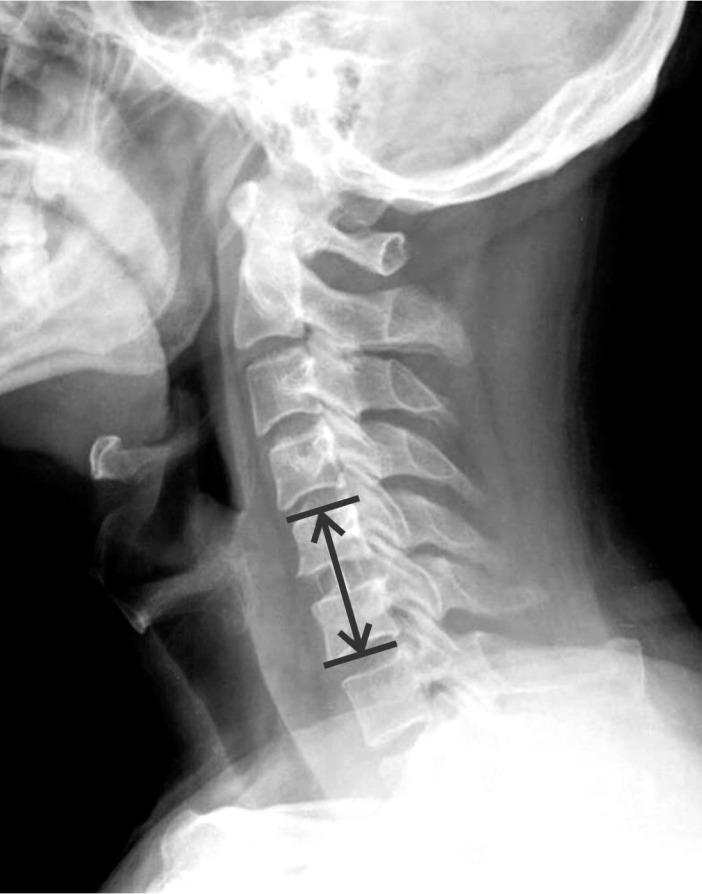

Patients with degenerative cervical disease who were diagnosed and treated in Konyang University Hospital between January 2004 and December 2014 were included in this study. Patients who had operation in single level ACDF were selected. Patients scored the degree of pain using visual analog scale before and after the surgery. Subsidence was defined as ≥3-mm decrease of the segmental height, and cervical kyphosis was defined as progression of ≥5° at 12 months after postoperative follow-up compared to that measured at the immediate postoperative period.

本研究纳入2004年1月至2014年12月在韩国公州大学医院诊断并接受治疗的退变性颈椎疾病患者。选取接受单节段ACDF手术的患者。患者在手术前后使用视觉模拟量表对疼痛程度进行评分。下沉定义为节段高度下降≥3mm,颈椎后凸畸形定义为术后12个月随访时相比术后即刻测量的后凸角度进展≥5°。